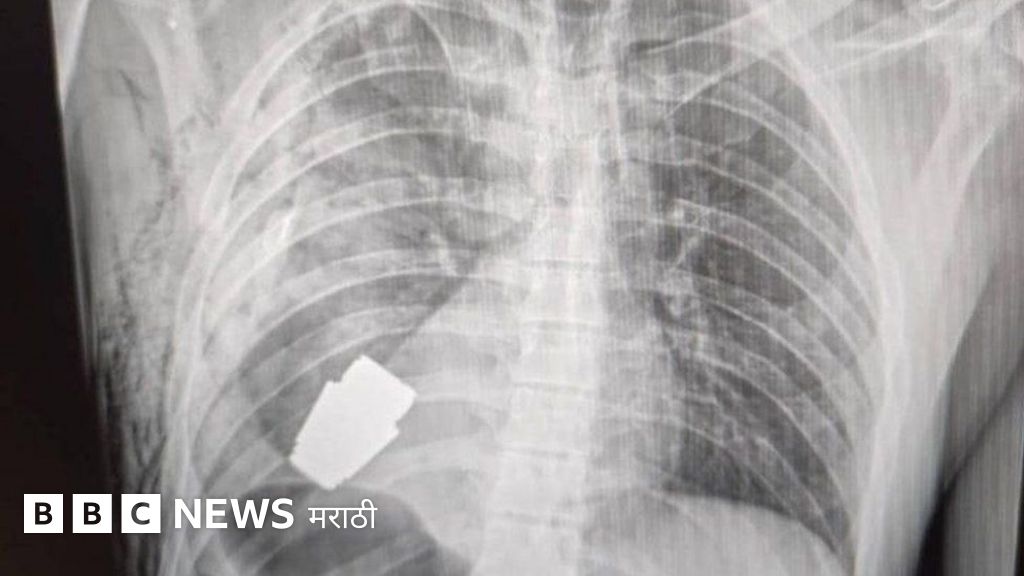

युक्रेनमधील एका सैनिकाच्या छातीमधून न फुटलेलं ग्रेनेड काढण्यात आलं आहे.

युक्रेनच्या सैनिकी वैद्यकसेवेने फेसबूकवर त्याचा एक्सरे फोटो प्रसिद्ध केला आहे. या सैनिकाच्या हृदयाच्या अगदी जवळ हे ग्रेनेड असल्याचं दिसतं.

हे ग्रेनेड त्या सैनिकाच्या छातीत कसं गेलं हे अद्याप समजलेलं नाही. पण ते VOG ग्रेनेड असल्याचं समजतंय. ते 4 सेंमी. आकाराचे असून त्याचा 400 मीटर अंतरापर्यंत मारा करता येतो.